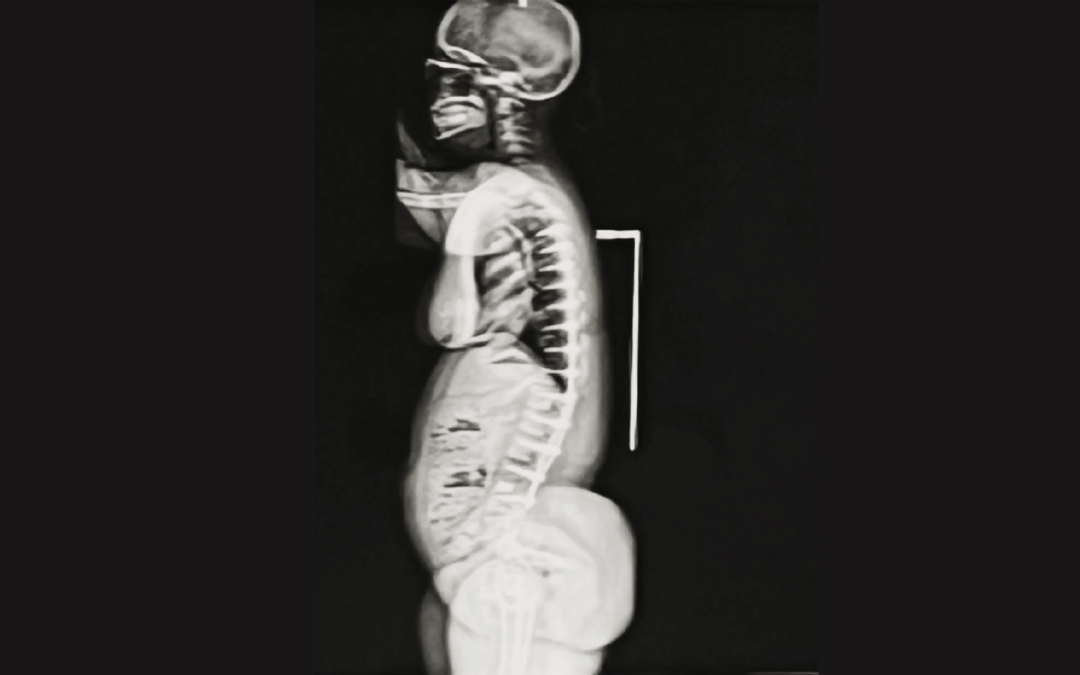

Understanding the Adult Achondroplasia Spine Adults with achondroplasia, the most common form of dwarfism, often experience progressive spine problems that impact mobility, comfort, and independence. The same skeletal characteristics that define the condition:...

Understanding the Achondroplasia Spine Achondroplasia is the most common form of skeletal dysplasia, caused by a genetic change in the FGFR3 gene that affects bone growth. While children with achondroplasia have average intelligence and life expectancy, their bone...